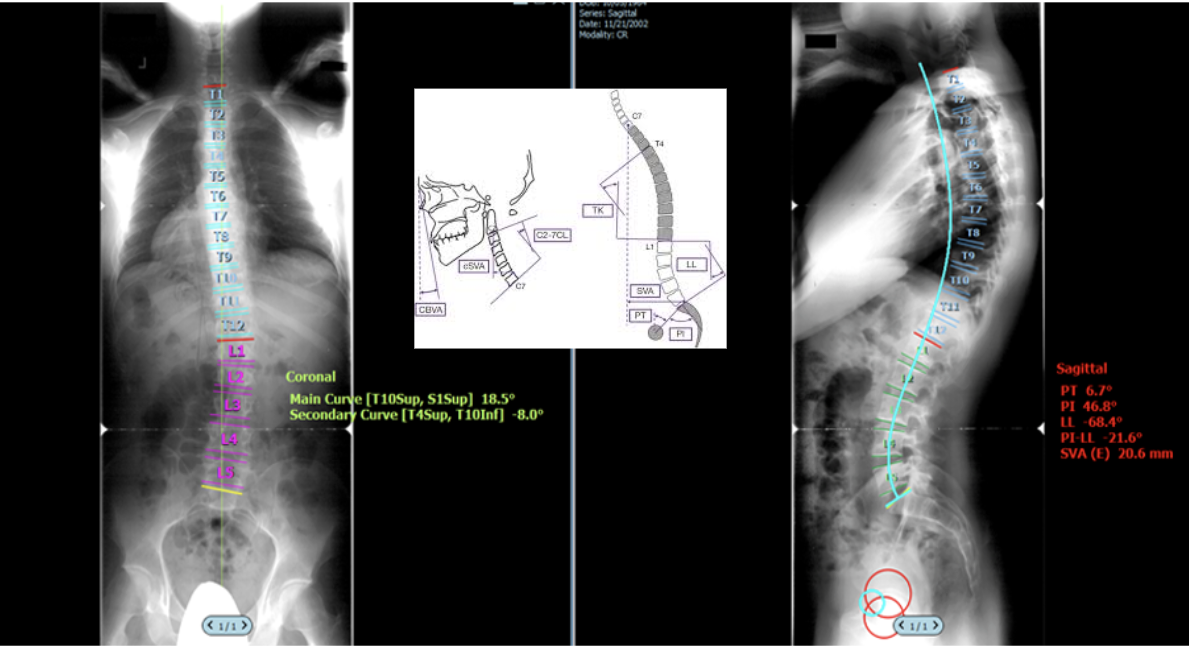

Surgimap is a widely used, spine-specific radiographic analysis and surgical planning software designed for evaluation of spinal alignment and deformity. It enables standardized measurement of coronal and sagittal parameters, including: Cobb angles, sagittal vertical axis (SVA), pelvic incidence (PI), pelvic tilt (PT), lumbar lordosis (LL), and segmental alignment; primarily from standing radiographs. Surgimap is extensively cited in the spine literature and has become a de facto reference standard for deformity assessment, preoperative planning, and postoperative outcome evaluation. Its intuitive interface and free availability have contributed to broad adoption among spine surgeons, trainees, and researchers worldwide.